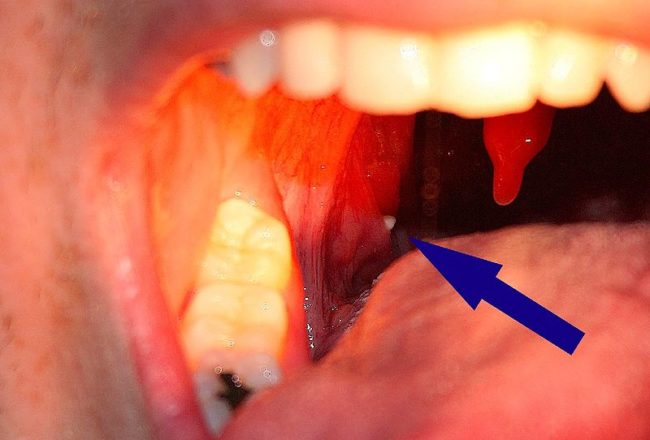

Hvítir kögglar

Það geta komið upp úr hálsinum hvítir kögglar sem eru mjög illa lyktandi. Það er tvímælalaust merki um að sýking sé í hálskirtlunum.